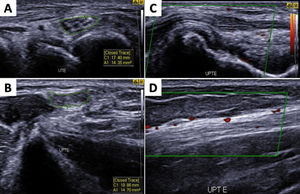

Ultrasonography showing asymmetric neuropathy at the left ulnar nerve with thickened transverse sectional areas in the cubital tunnel (A-UTE) and in the distal region of the arm (B-UPTE) with hyperechoic perineurs and evident fascicular distention (C), in addition to blood flow in the epineural and intraneural region (D) as a sign of active neuritis.

As published before by Frade et al.,8 we analyzed the cross-sectional areas (CSA) in median nerves (carpal tunnel and distal forearm), ulnar nerves (cubital tunnel and distal arm), common fibular nerves (head of fibula and distal thigh) and tibial nerves (posterior to the ankles). Nerve asymmetry was calculated by the difference between the biggest and the smallest CSA in the same nerve point. Nerve focallity was calculated by the difference between two points (proximal and distal CSA) in the same nerve. Qualitative morphological alterations were defined by loss of fascicular nerve pattern, heterogeneous fascicular distention, signs of perineural fibrosis. The intra-nerve Doppler positive sign is indicative of active neuritis.

Ultrasonography is a technique that allows good quantitative and qualitative representation of peripheral, superficial and deep nerves by measuring cross sectional areas and provides information about echotextural changes and fascicular patterns in neuropathies, which allow the detection of asymmetry and focallity of peripheral nerve thickening.8,10 Ultrasound evaluation was in line with the multibacillary classification of the patients, since 100% showed nerve thickening, even in those presenting only hypochromatic macular lesions, as clinical signs.

DiscussionThe decline in leprosy prevalence and the commitment to leprosy elimination as a public health problem in many countries have been accompanied by a decline in disease expertise.9 Leprosy can mimic many common dermatological and neurological conditions,4,5 leading to delays in diagnosis. However, even in the presence of anesthetic lesions with thickened nerves, hallmarks signs, many physicians seem to lack the skills to diagnose leprosy, even the classic forms. In routine, almost exclusively neuritis is considered an emergency in leprosy, an exclusive sign to justify emergency care because of acute neural damage and sensory and/or motor disability. Surprisingly, all our patients had a history of chronic neural pain, longer than three months, but only four of them showed neuritis on ultrasound (positive intraneural Doppler signal). Additionally, all patients had altered feet tactile sensitivity test, also defining the pattern of asymmetrical and focal multiple mononeuropathy in leprosy diagnosis, and also for the clinical-therapeutic follow-up.